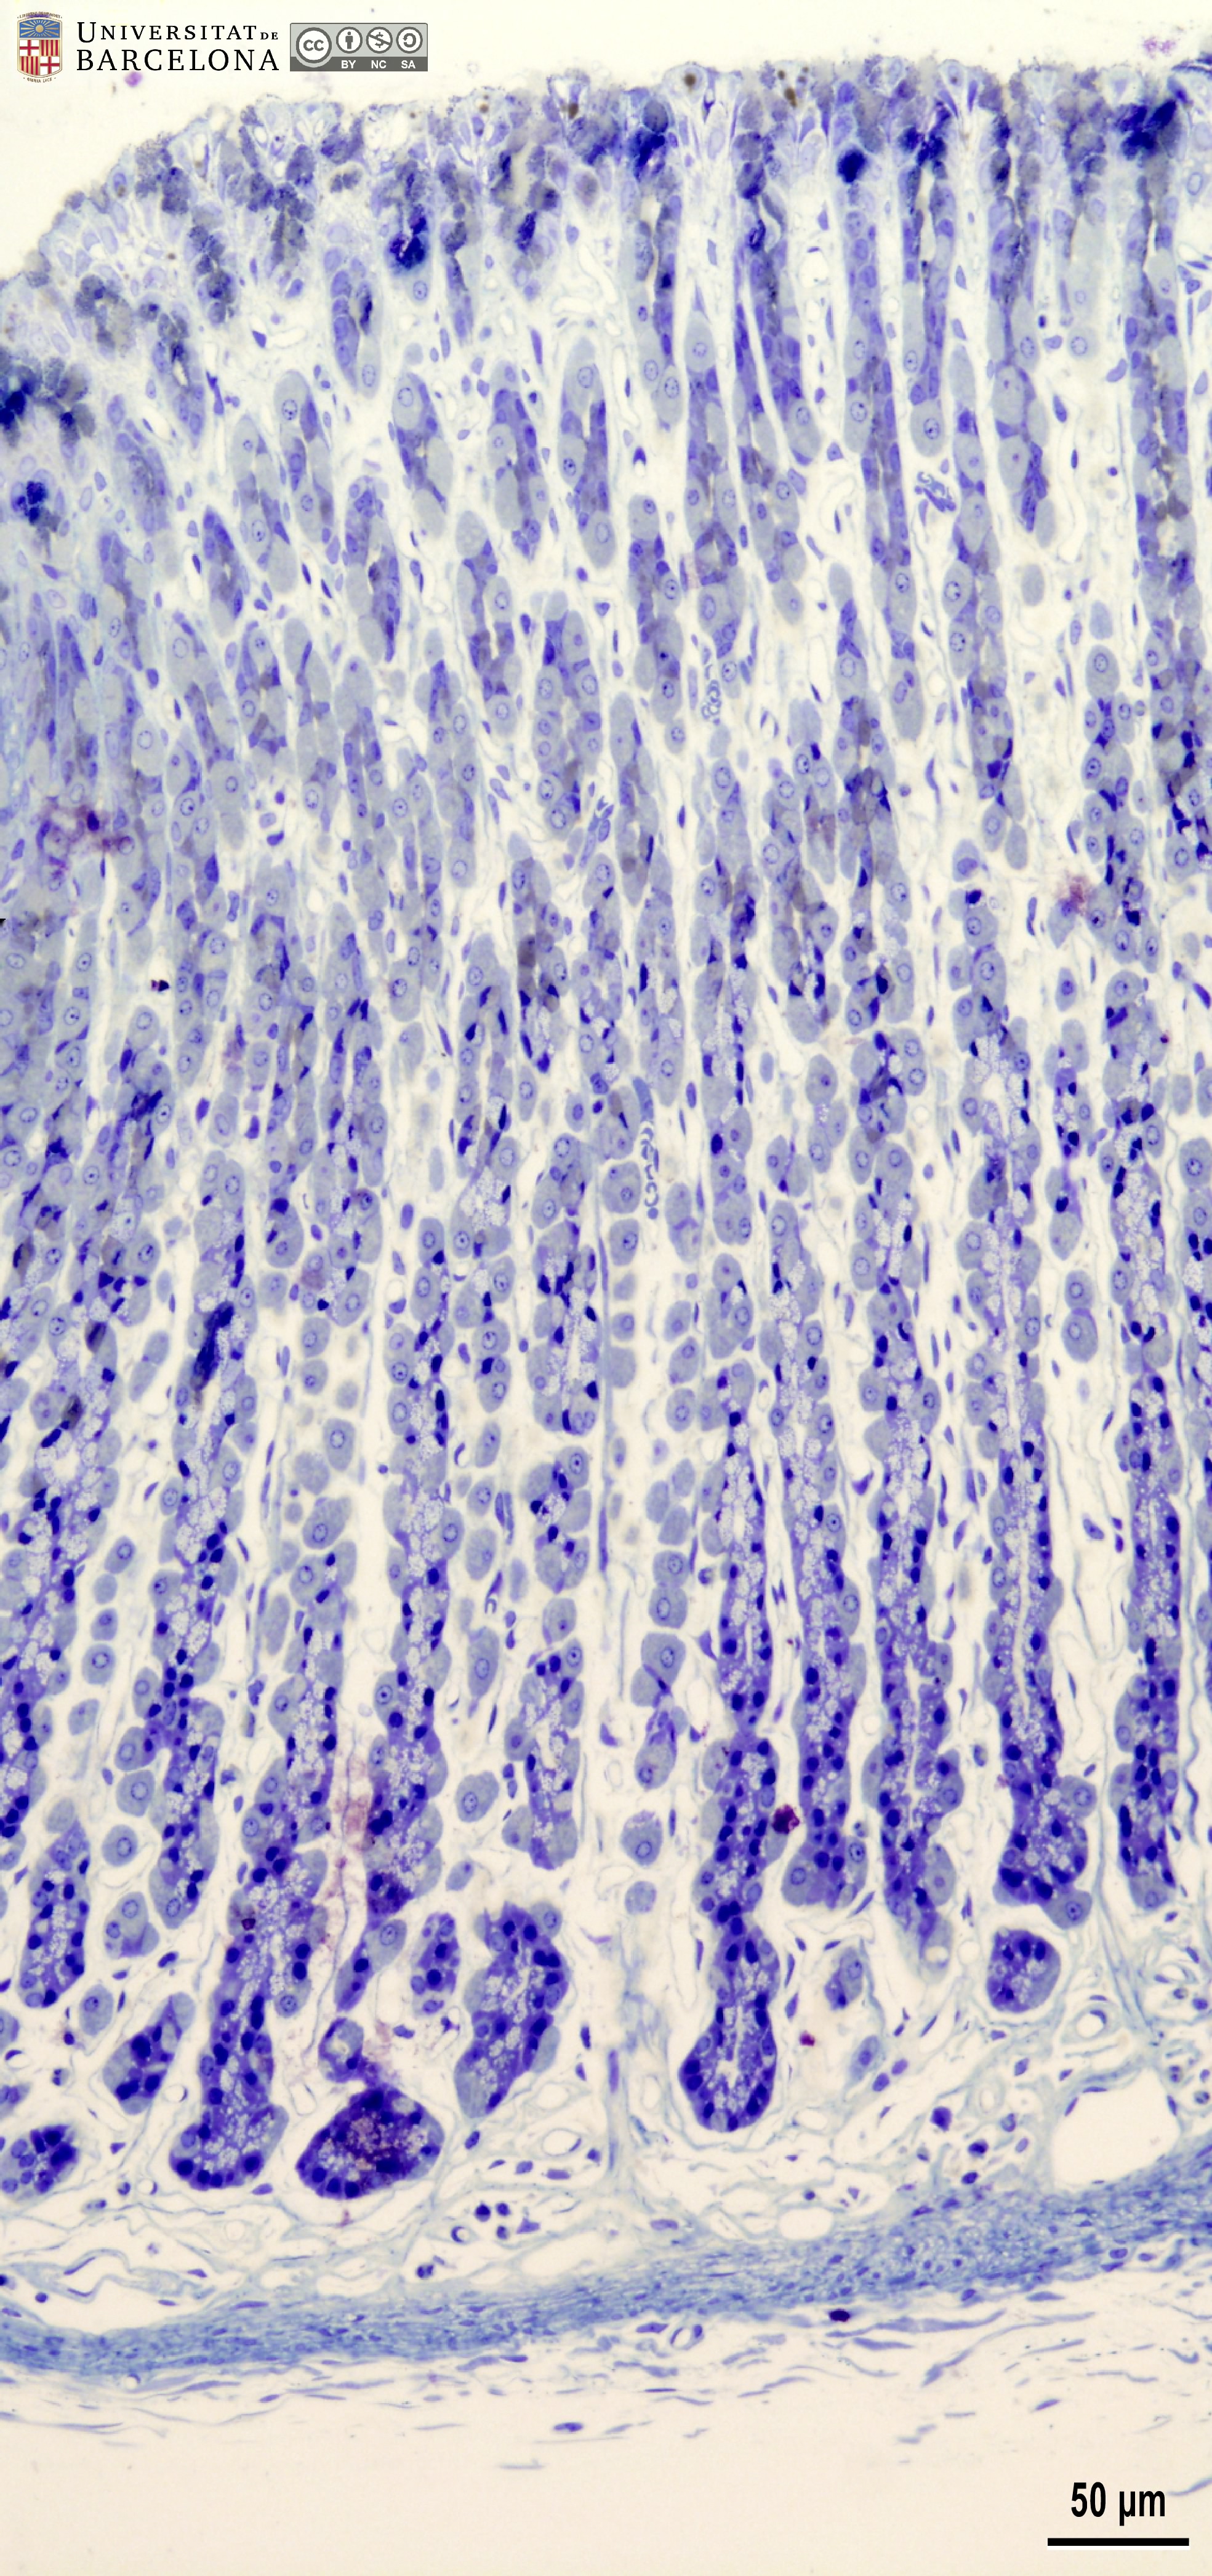

Stomach: histological organisation of the gastric wall

[ENG] A collection of micrographs illustrating the organisation of the stomach in rats. The layers of the gastric wall and their components –such as blood vessels, fibres and cell types– are shown in paraffin sections stained with hæmatoxylin-eosin stain or van Gieson trichrome. Semithin sections 2 µm thick were stained with toluidine blue. This collection complements the micrographs published by Dr Elena Sagristà i Mateo https://hdl.handle.net/2445/60213 — See also: https://diposit.ub.edu/dspace/browse?type=author&value=Sagrist%C3%A0+i+Mateo%2C+Elena

Cite as: Pérez-Clausell J (2025). Stomach: histological organisation of the gastric wall. Universitat de Barcelona. Departament de Biologia Cel·lular, Fisiologia i Immunologia. Dipòsit digital UB [consulted on 7/23/2025] https://hdl.handle.net/2445/222504